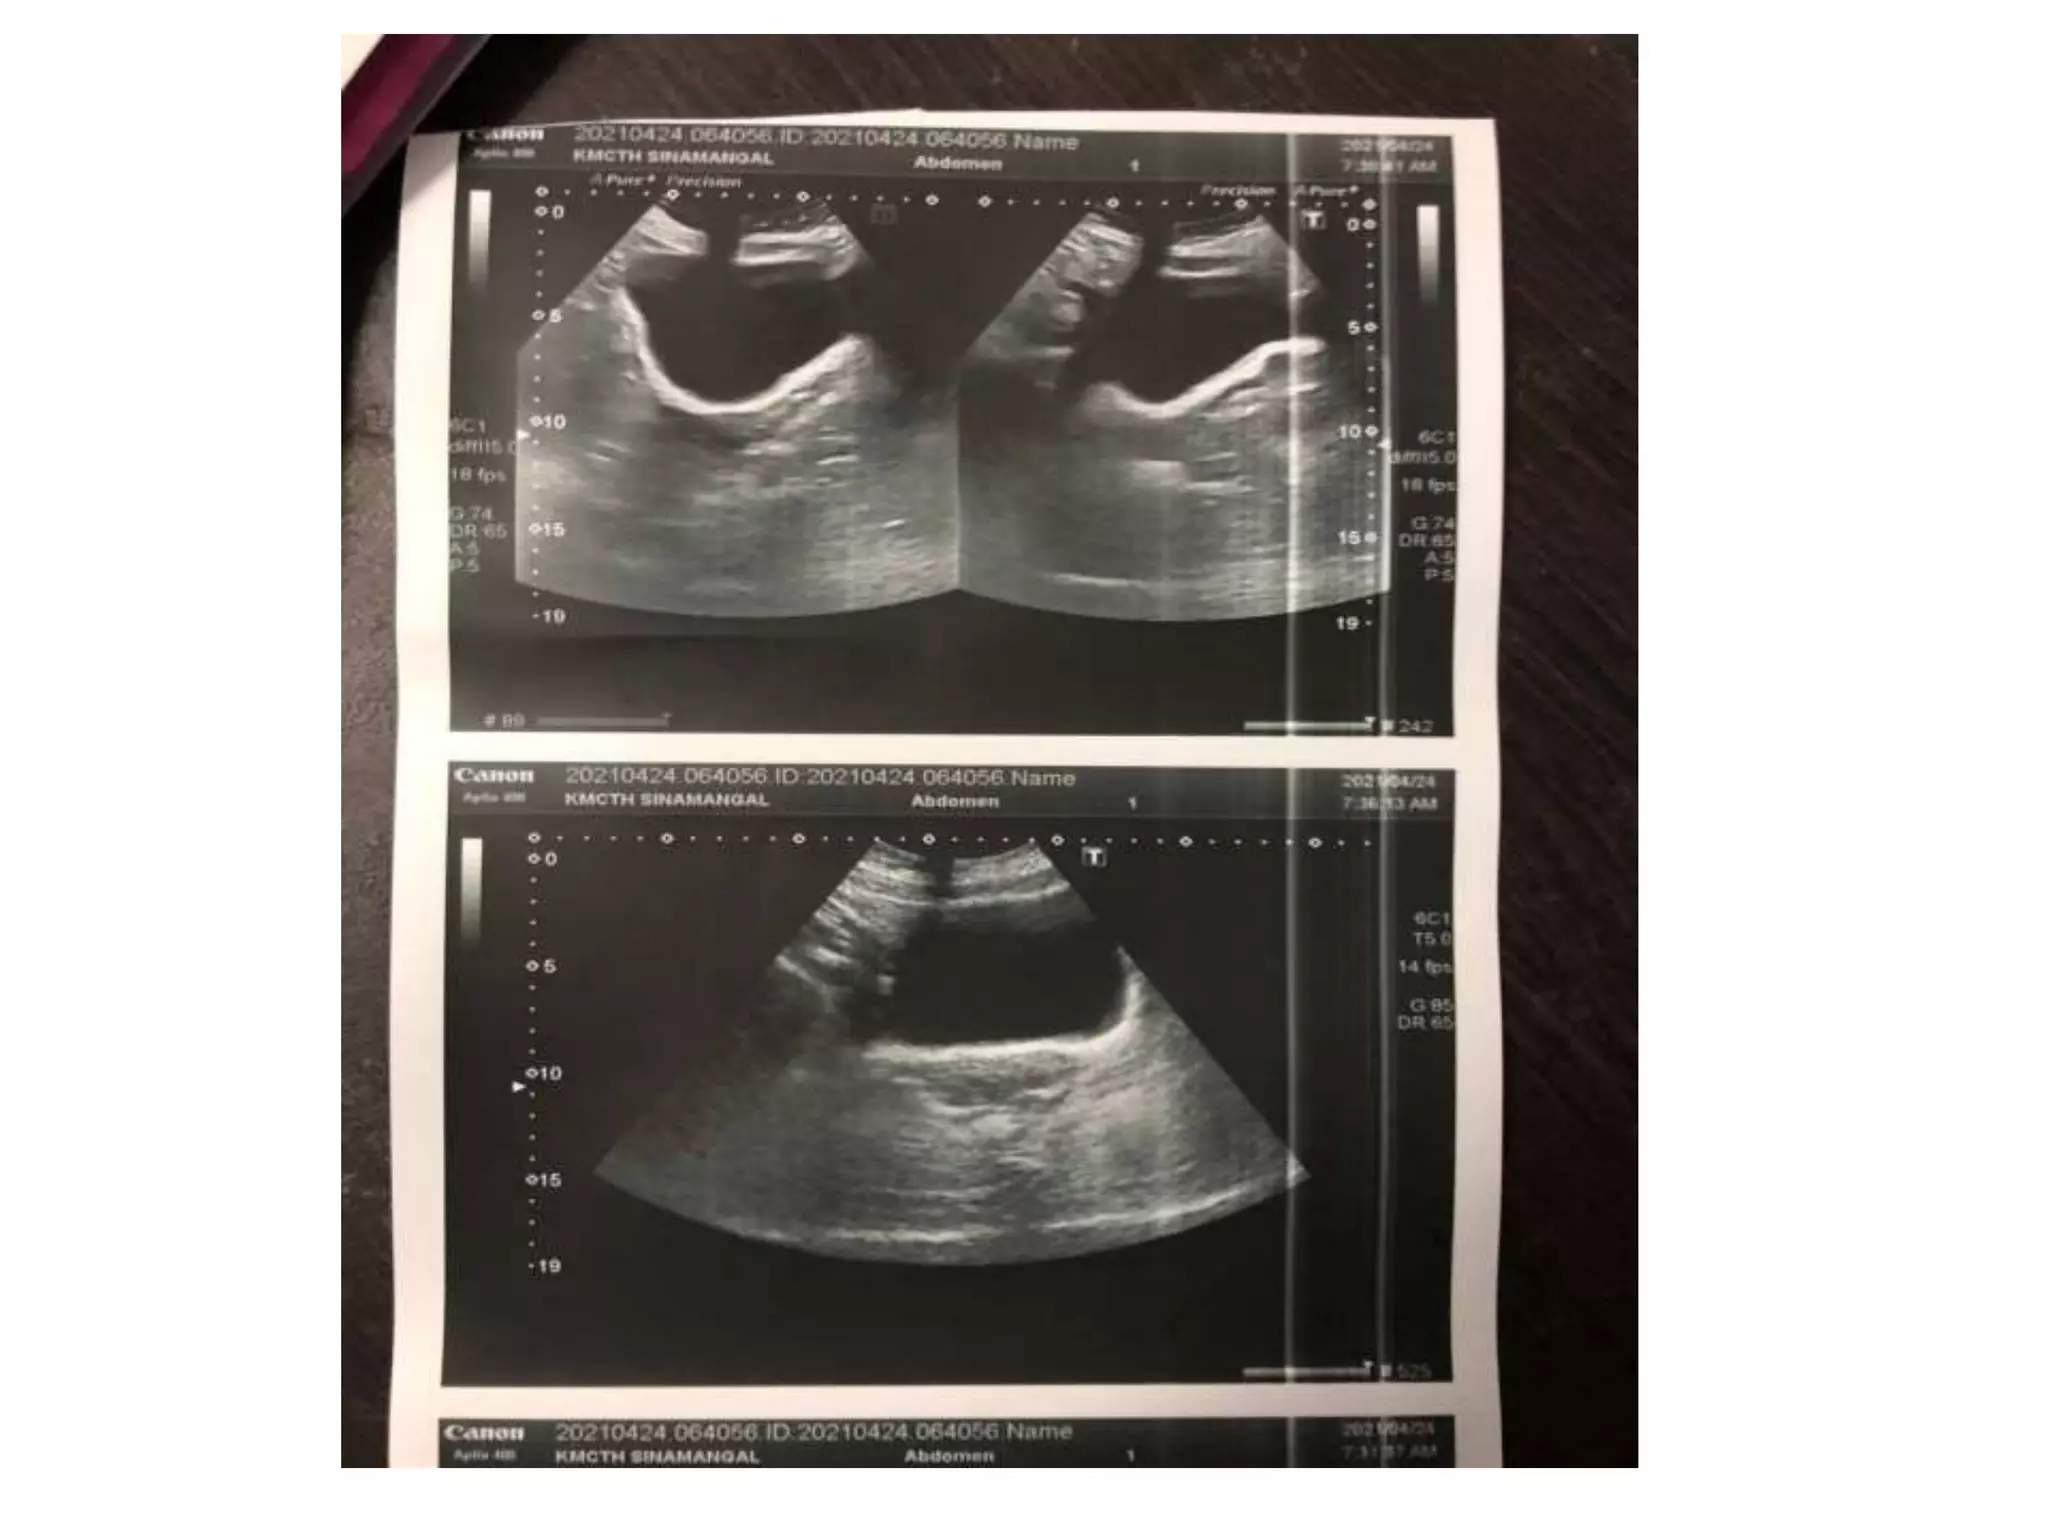

A 35-year-old woman presented with severe lower abdominal pain and difficulty urinating. An ultrasound revealed she had two separate uteruses with separate cervical canals but a normal vaginal canal, consistent with a bicornate bicollis uterus. This type of uterus is a müllerian duct anomaly that can result from interrupted development of the müllerian ducts in utero. Müllerian duct anomalies are associated with renal, vertebral, and cardiac anomalies as well as infertility and menstrual disturbances.